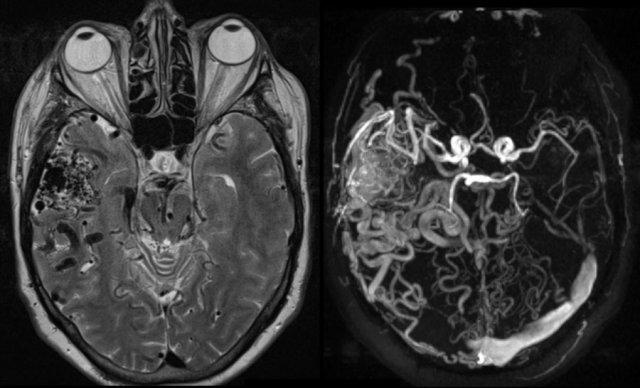

Chuỗi xung T2W (trái) và MRA tương phản pha (phải) cho thấy dị dạng động-tĩnh mạch nội sọ (AVM) nằm ở hố thái dương phải.